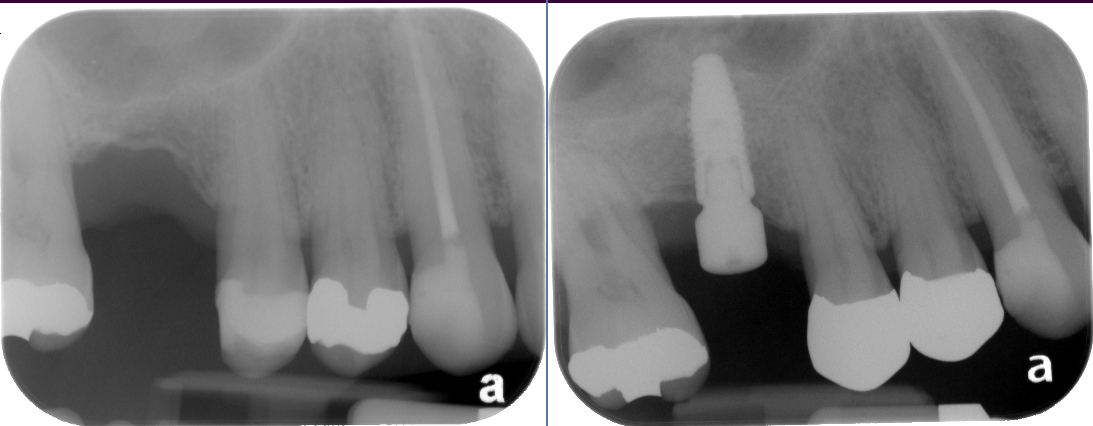

The key to a successful and long-lasting dental implant is the quality and quantity of jaw bone to which the implant will be attached. If bone loss has occurred due to injury or periodontal disease, a sinus augmentation can raise the sinus floor and allow for new bone formation.

In the most common sinus augmentation procedure, a small incision is made on the premolar or molar region to expose the jaw bone. A small opening is cut into the bone, and the membrane lining the sinus is pushed upward. The underlying space is filled with bone grafting material, either from your own body or from a cadaver. Sometimes, synthetic materials that can imitate bone formation are used. After the bone is implanted, the incision is stitched up and the healing process begins.

After several months of healing, the bone becomes part of the patient’s jaw and dental implants can be inserted and stabilized in this new sinus bone.

If enough bone between the upper jaw ridge and the bottom of the sinus is available to stabilize the implant well, sinus augmentations and implant placement can sometimes be performed as a single procedure. If not enough bone is available, the sinus augmentation will have to be performed first, then the graft will have to mature for several months, depending upon the type of graft material used. Once the graft has matured, the implants can be placed.